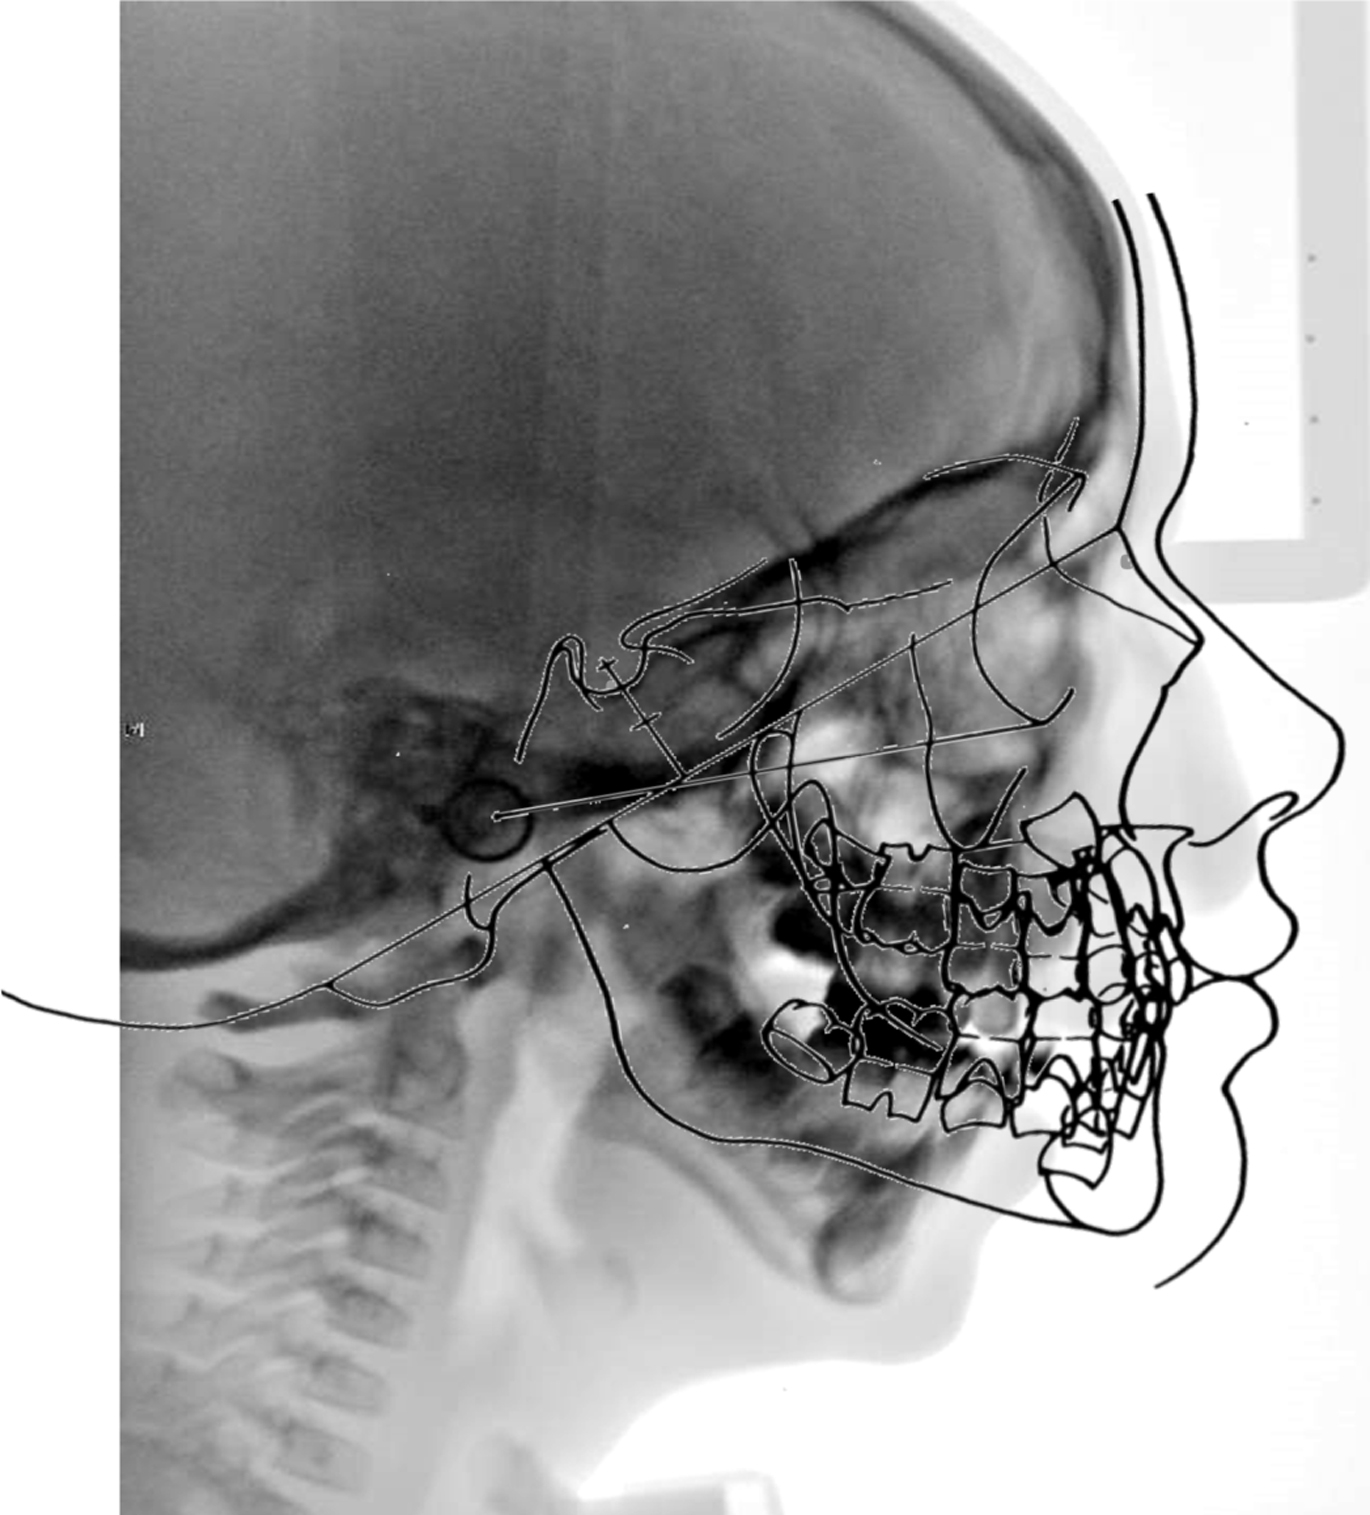

The primary indication for C3DO is severe airway obstruction with tracheostomy dependence in the setting of maxillomandibular deficiency and a high occlusal plane ( Fig. 1 ). Many patients who undergo this operation have had unsuccessful attempts to remove the tracheostomy tube using other procedures, including isolated mandibular distraction, and often are dependent on gastrostomy tube for feeding. In addition to Treacher Collins syndrome, severe presentations of other conditions, such as craniofacial microsomia and acrofacial dysostosis, also have benefited from this operation.